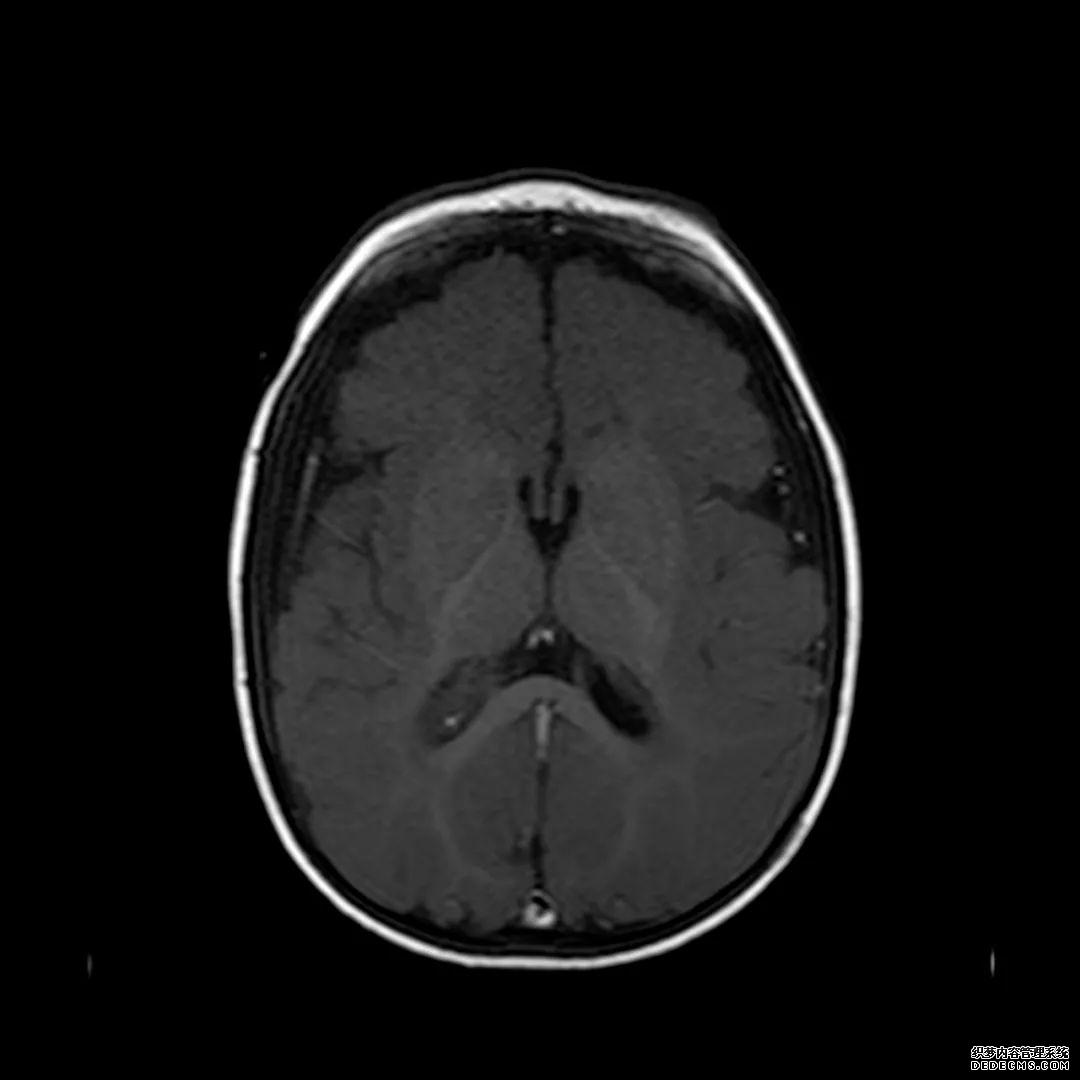

脑MRI显示尾状核、扁豆状核和脑梗头部T2/FLAIR呈双侧对称异常高信号。扩散限制涉及这些区域,其特征是扩散加权DWI(B-1000)上的高强度,ADC图上相应的减弱强度。

印象:通过将这些成像模式与临床和实验室检查结果相结合,就有可能得出低血糖性脑病。

低血糖性脑病是一种代谢性脑病,它是由脑细胞对葡萄糖的供应和使用之间的不平衡引起的。脑MRI,尤其是DWI是诊断和预测该病预后的重要工具。

这个病例说明了低血糖脑病,有典型的病史和血液指标,结合MRI表现,DWI为诊断提供了最好的线索。

影像影响内囊后肢、大脑皮层(特别是枕叶和岛叶)、海马和基底节区,常是双边对称性的。